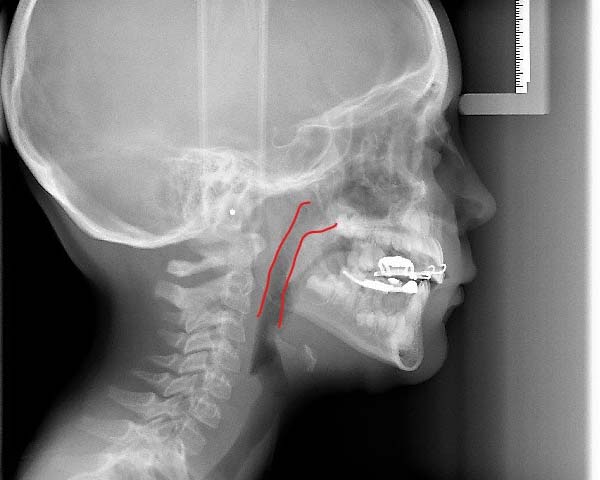

The best age is as soon as it is suspected there are airway issues, our youngest patient is 2.5 years old. The sooner we recognize an airway issue, the greater the chances of achieving harmonious physical and neural growth and development. Below are examples of patients in our practice who have undergone airway development for pediatric sleep apnea or sleep disordered breathing:Adults

We recognize many adults need expansion treatment but that becomes more difficult as we age. Adults with sleep disordered breathing present with many symptoms that can include, snoring, open mouth breathing, sleep apnea, upper respiratory resistance syndrome, and trouble falling or staying asleep. The goal is to determine why these symptoms are present and what can be done to improve the patient’s quality of life with appliances or surgical recommendations. Dr. Kuhta uses specialized bone supported expanders to change the shape of the jaw and not just mask the problem. Every treatment plan is specialized to your needs and aims to alter the way in which you breathe. Dr. Kuhta offer’s non-surgical and minimally invasive surgical options to expand or widen the upper jaw. Using bone-based expanders the goal is to widen the jaw and not just tip the teeth. By expanding the jaw with TAD-based (or mini implant) expanders, you can improve airway, increase room for the tongue, open the nasal cavity and correct crossbites. Skeletal expansion on adults can be life changing! If you are interested in the maxillary skeletal expander (MSE) your next step is scheduling an airway consultation. From there we determine if you are a possible candidate and progress to 3-D imaging to evaluate the probable success of expansion. Before your appointment if you would like to research MSE appliances, Dr. Kuhta would be happy to answer any specific questions.